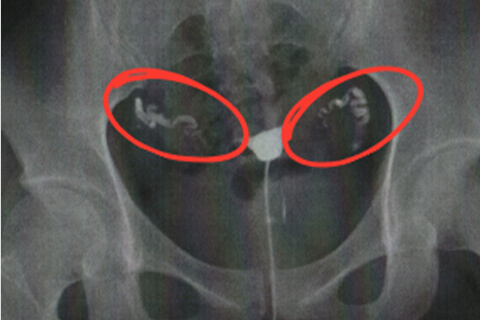

子宮卵管造影検査を行うことで卵管の閉塞や狭窄がないか調べることができます。検査は5分ほどで、痛みは通常はほとんどありません。卵管が狭窄している場合痛みを感じることがあります。麻酔は必要ありません。再診料・抗生剤等も合わせて約5,000円弱です。 子宮頚管から細いチューブを挿入し、その先端に付いたバルーンを膨らませて子宮内に固定します。造影剤を流しながらX線透視を行い、子宮の内部、卵管、腹腔まで造影剤が拡散していく様子を観察します。

両側閉塞

卵管が左右とも閉塞や狭窄している状態です。両側閉塞では自然妊娠の可能性が限りなく低いため卵管鏡下卵管形成術が第一選択となります。

卵管性不妊症であることがわかった場合、卵管鏡下卵管形成術(FT)を実施し卵管の閉塞や狭窄を解消します。 月経が終了してから次の排卵日までの間に行うのが標準です。